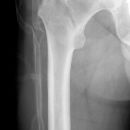

pertrochantäre Femurfraktur